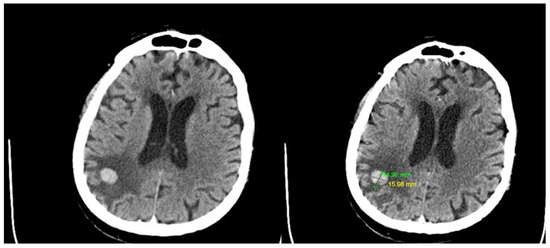

4.2. First Admission

4.3. Second Admission